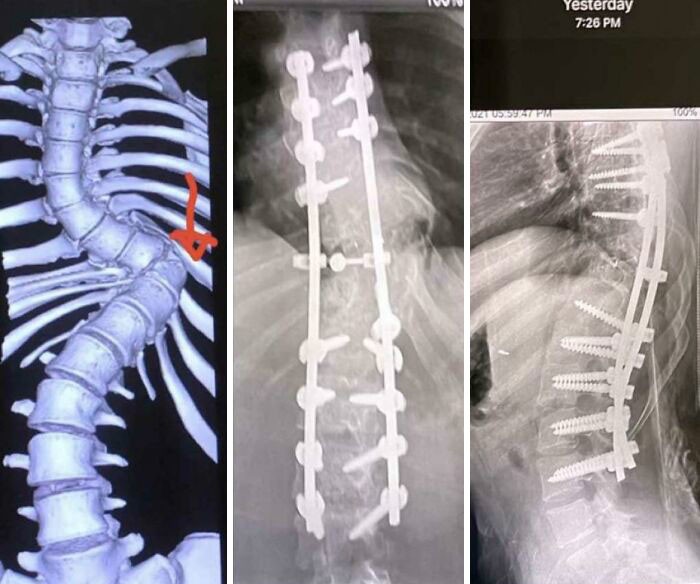

11. "У моего приятеля сколиоз, это фото с его операции"